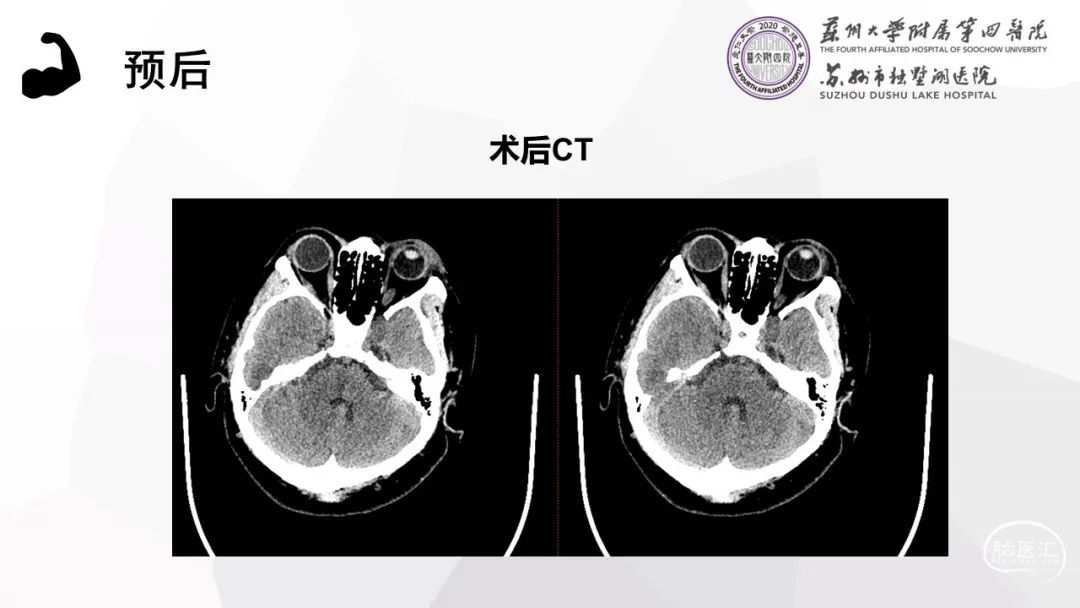

本期独术医志是由科室主任黄煜伦教授带来的双镜联合下经翼点硬膜外入路三叉神经鞘瘤(V1)切除术,虽然患者肿瘤不大,但是在有限的空间内运用神经内镜抵近观察特点,切除盲区、死角的残余肿瘤,做到影像学肿瘤全切,并且充分地保护了神经功能。